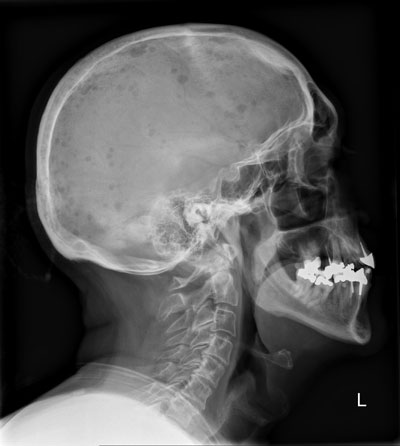

Ein 67-jähriger Patient kommt zu Ihnen mit diffusen Knochenschmerzen. Er klagt zudem über Müdigkeit, Abgeschlagenheit, Gewichtsverlust und Nachtschweiss.

Klinisch fällt eine Druck- und Klopfschmerzhaftigkeit des Skeletts v.a. entlang der Wirbelsäule und Hüfte auf. Mit blossem Auge sind sichtbare Deformierungen und Erhebungen im Bereich des Schädels erkennbar, woraufhin zunächst ein Schädelröntgen erfolgt.

Das Seitenbild des Schädels sehen Sie hier: